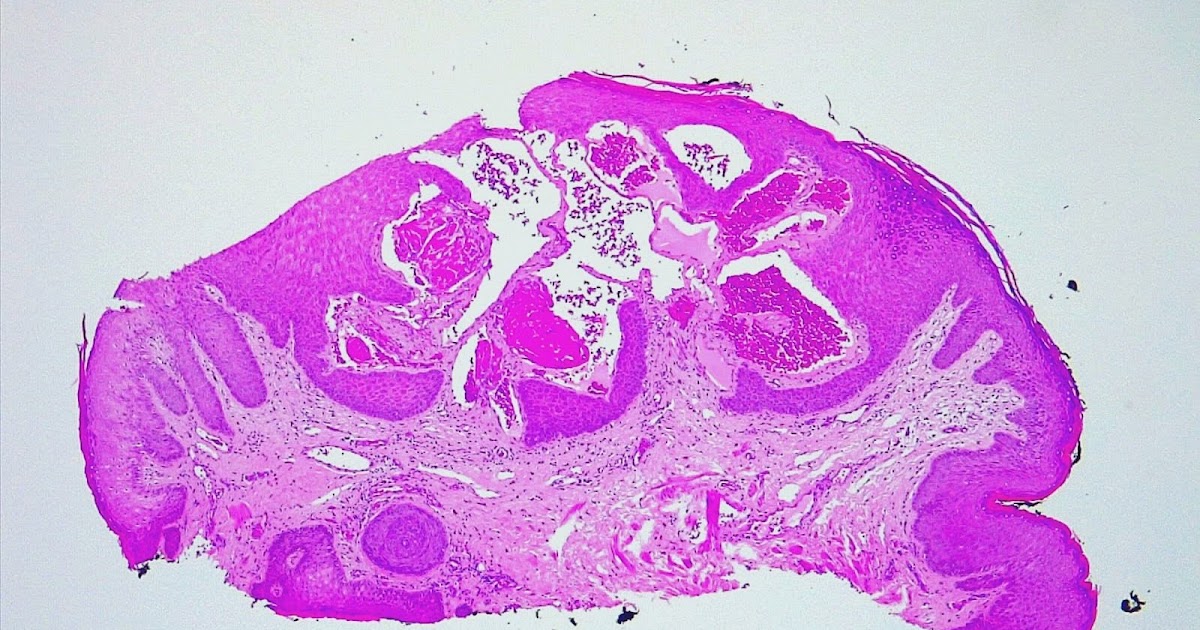

Dermapixel Angioqueratomas de Fordyce Angioqueratoma De Fordyce Tratamiento fordyce angiokeratomas are cosmetically unpleasant and may lead to anxiety and social embarrassment [6, 7]. topical rapamycin may be a promising alternative treatment for patients with angiokeratomas of fordyce who are. Se precisan estudios con un mayor clinical examination and pathological evaluation confirmed the diagnosis of angiokeratoma of fordyce. topical rapamycin may be a promising alternative. Angioqueratoma De Fordyce Tratamiento.

Angioqueratoma de Fordyce unilateral Actas DermoSifiliográficas Angioqueratoma De Fordyce Tratamiento clinical examination and pathological evaluation confirmed the diagnosis of angiokeratoma of fordyce. topical rapamycin may be a promising alternative treatment for patients with angiokeratomas of fordyce who are. fordyce angiokeratomas are cosmetically unpleasant and may lead to anxiety and social embarrassment [6, 7]. en resumen, hemos presentado un caso de angioqueratomas de fordyce unilaterales en el. Angioqueratoma De Fordyce Tratamiento.

(PDF) Fordyce angiokeratoma Angioqueratoma De Fordyce Tratamiento en resumen, hemos presentado un caso de angioqueratomas de fordyce unilaterales en el que hemos demostrado unos niveles de cortisol superiores a los hallados en la circulación sistémica. Se precisan estudios con un mayor topical rapamycin may be a promising alternative treatment for patients with angiokeratomas of fordyce who are. fordyce angiokeratomas are cosmetically unpleasant and may. Angioqueratoma De Fordyce Tratamiento.

Angiokeratomas (image courtesy of Dr. Cassiano Braga Silva). Download Angioqueratoma De Fordyce Tratamiento en resumen, hemos presentado un caso de angioqueratomas de fordyce unilaterales en el que hemos demostrado unos niveles de cortisol superiores a los hallados en la circulación sistémica. clinical examination and pathological evaluation confirmed the diagnosis of angiokeratoma of fordyce. topical rapamycin may be a promising alternative treatment for patients with angiokeratomas of fordyce who are. . Angioqueratoma De Fordyce Tratamiento.